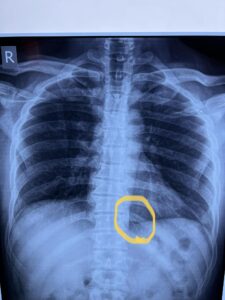

تمكن فريق جراحي بمستشفى بنها الجامعي بمحافظة القليوبية، في استخراج إبرة تنجيد دخلت عن طريق الخطأ في ظهر مريض خلف القفص الصدري مباشرة، والتي ظلت بمكانها مدة عامين.

وأوضحت المستشفى، في بيان لها اليوم، أنه جرى إجراء جراحة بفتح جراحي صغير 3 سم، استخراج “إبرة تنجيد”، دخلت بطريق الخطأ في ظهر مريض خلف القفص الصدري مباشرة، حيث تركها المريض لمدة سنتين خوفا من إجراء العملية.

وتابعت، أنه تم حجز المريض بالقسم وتجهيزه لعملية سريعة، جرى فيها الاستعانة بجهاز الأشعة الملحق بغرف العمليات (C-arm)، حيث تم تحديد مكان الإبرة والفتح الجراحي عليها مباشرة، واستخراجها بنجاح ،ولكن على هيئة قطع منكسرة بسبب الصدأ، نظرا لبقائها طوال هذه المدة.